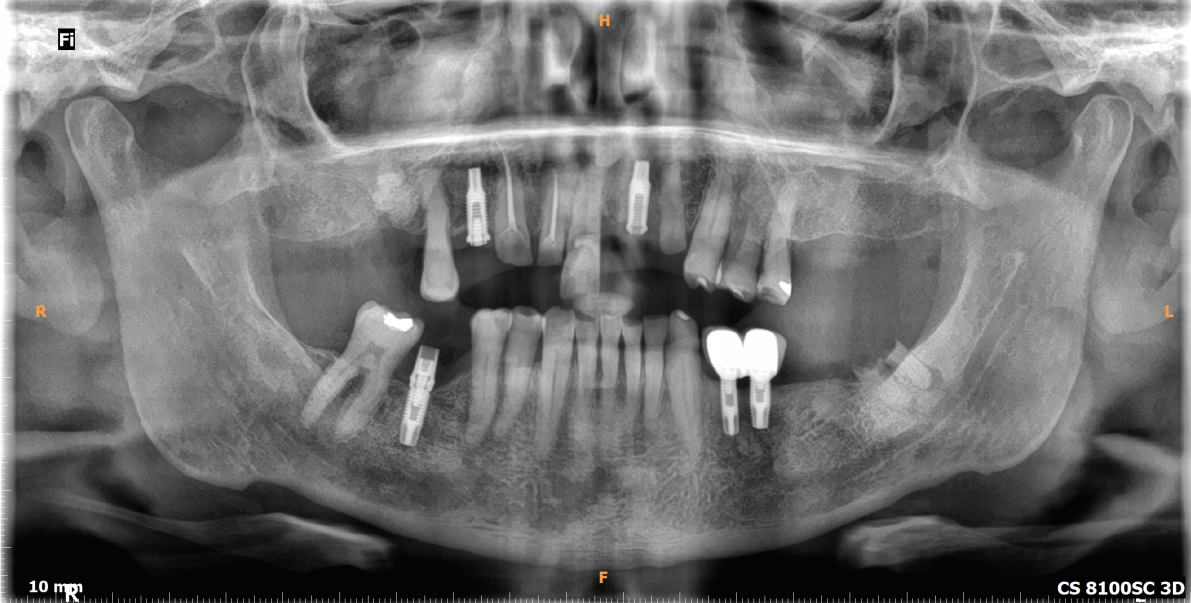

DIAGNÓSTICO: Presenta riesgo y actividad de caries, periodontitis estadío II grado A generalizada, brechas desdentadas clase III del sector I y II (de 15-17 y de 25-27) y sector III (de 35 a 37).

PLANIFICACIÓN: Se presentaron 3 planes de tratamientos, finalmente se decidió realizar reconstrucción fija superior e inferior.

TERAPIA: Terapia básica, complementaria y mantenimiento.